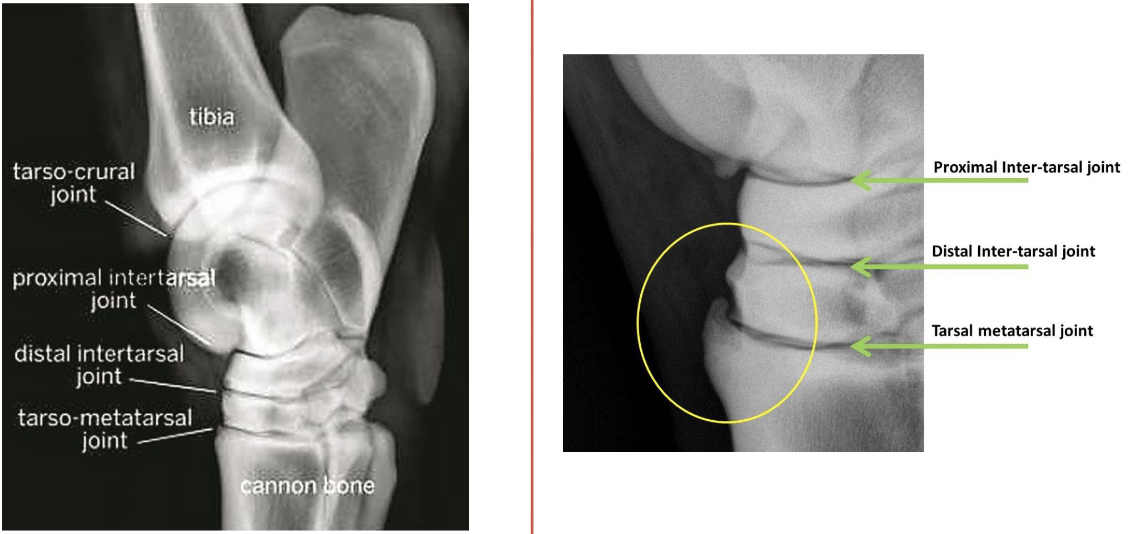

what are the bones of the tarsus

distal tibia, calcaneus + sustentaculum tali (fused), talus (+ medial and lateral trochlea), central tarsal bone, 3rd tarsal bone, 4th tarsal bone, fused 1 & 2 tarsal bone, proximal 2 3 and 4 metatarsal bones

joints of the tarsus

red- tibiotarsal (or tarsocrural)

green- proximal intertarsal

blue- distal intertarsal

purple- tarsometatarsal

which joints of the tarsus communicate w/ e/o

tibiotarsal and proximal intertarsal joints

which tarsal joints are the most common sites of arthritis in horses

distal intertarsal and tarsometatarsal

degenerative joint disease “arthritis”

a radiographic diagnosis

most common location in horse are distal tarsal joints: distal intertarsal, tarsometatarsal

what are the radiographic abnormalities that dx arthritis (in order of apperance)

osteophytes & enthesiophytes (bone spurs)

joint space thinning

subchondral bone sclerosis (more opaque)

periosteal proliferation (sunburst, more mineralized on surface of bone)

subchondral bone lysis (darker on rad)

ankylosis (joint fusion)

what is this

distal tarsal joint osteoarthritis (OA)

what is circled on image on the right

osteophyte (bone spur, body is trying to fuse joint)

patient has distal tarsal joint osteoarthritis